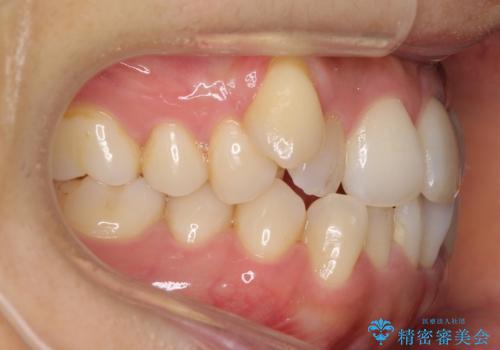

八重歯 上下の正中のずれ 40代で抜歯矯正

- 八重歯と上下の正中のずれを気にして来院。

上の前歯の正中が右にずれていました。

小臼歯抜歯を行い、ワイヤー矯正を行いました。